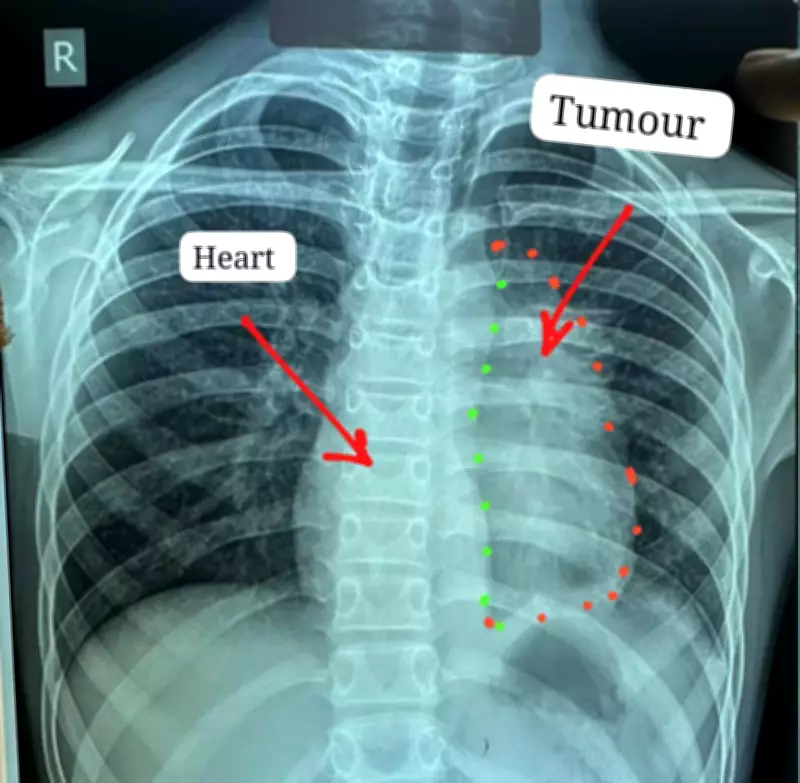

The young patient had been suffering from persistent chest pain, heaviness, and breathlessness for about six months before diagnosis. Medical investigations revealed a substantial tumor in his chest cavity that was tightly adherent to critical structures including the heart and major blood vessels. After several hospitals reportedly declined to operate due to the extreme risks involved, the boy was referred to Ambedkar Hospital for specialized care.

The tumor presented extraordinary surgical challenges due to its extensive involvement with multiple vital organs. According to the medical team, the cancer had spread to involve the heart, pericardium, phrenic nerve, aorta, main pulmonary artery, left atrium, and part of the lung. Such cases are considered among the most difficult in thoracic oncology, with complete tumor removal often deemed nearly impossible.

The tumor was later identified as invasive thymic carcinoma, specifically type-B thymoma at stage 3. This cancer typically affects individuals between 40 and 60 years of age and is exceptionally rare in pediatric patients. To address this complex case, surgeons employed a dual-approach technique combining both sternotomy and thoracotomy procedures.

This involved making incisions through both the breastbone and chest wall to access the tumor, which measured approximately 12x8 centimeters and weighed nearly 400 grams. The four-hour procedure was conducted with a heart-lung machine kept on standby for potential emergencies, highlighting the meticulous preparation undertaken by the surgical team.